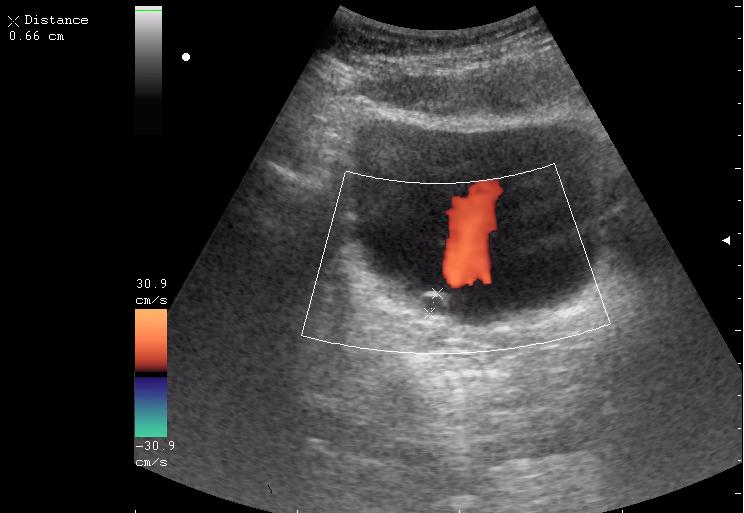

Сравните

Продольное сканирование мочевого пузыря После легкой перкуссии мочевого пузыря

Богу богово, кесарю - кесарево (я про анализы и клинические данные). На сонограммах неубедительно продемонстрирован осадок да и стенки м.п. не утолщены.